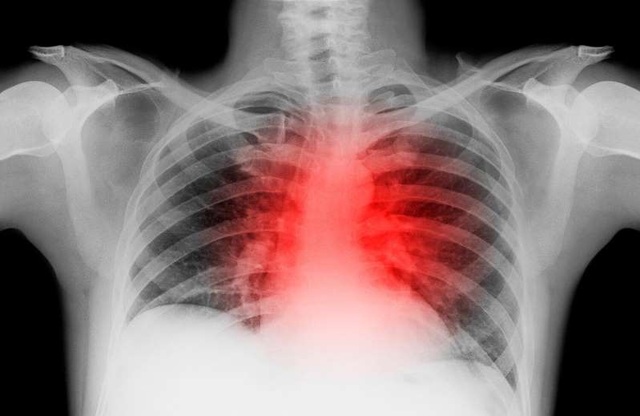

(Dân trí) - Hơn nửa năm sau đại dịch COVID-19, các chuyên gia cho rằng SARS-CoV-2 không chỉ gây bệnh về đường hô hấp, tấn công ở phổi mà nó có thể để lại tổn thương tim lâu dài sau nhiều tháng khỏi bệnh.

Các nhà nghiên cứu đã kiểm tra hình ảnh chụp cộng hưởng từ (MRI) tim của 100 bệnh nhân COVID-19 đã khỏi bệnh trong độ tuổi từ 45 đến 53 và so sánh với MRI của những người tương tự không nhiễm virus. Hầu hết các bệnh nhân COVID-19 đã hồi phục tại nhà, trong khi 33 bệnh nhân phải nhập viện tại một thời điểm nào đó.

Trong số 100 bệnh nhân COVID-19, 78 người có thay đổi cấu trúc tim. Trong nhóm này, 76 bệnh nhân có chỉ dấu sinh học thường thấy ở những bệnh nhân bị đau tim, và 60 bị viêm cơ tim. Tất cả các bệnh nhân “hầu như đều khỏe mạnh trước khi bị bệnh”, các nhà nghiên cứu cho biết.